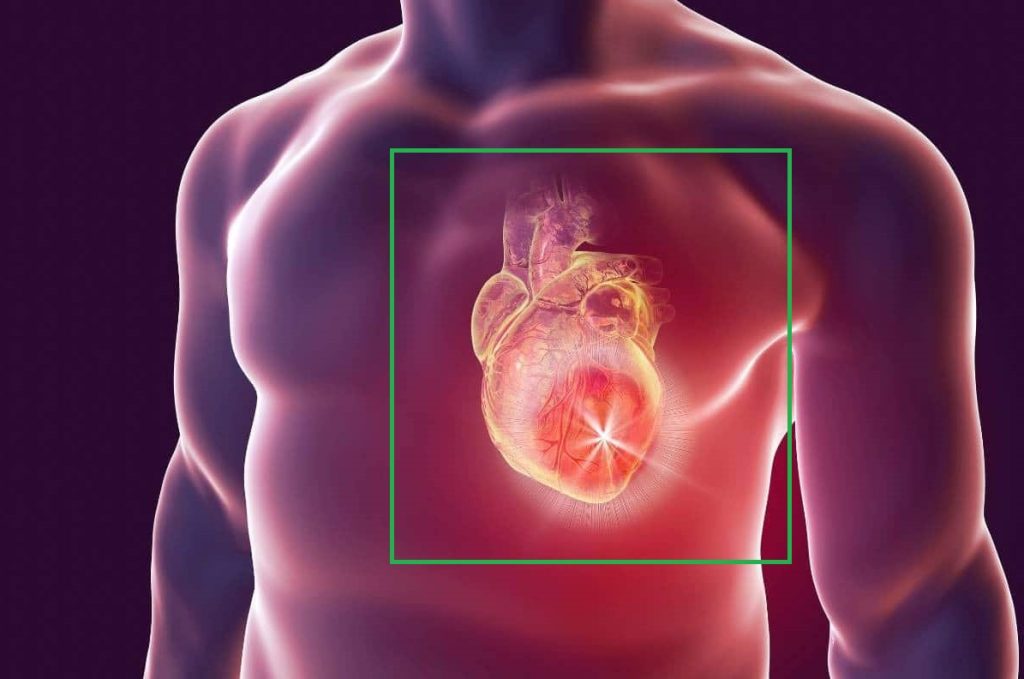

Hoy en día, se estima que entre el 5% y el 20% de las emergencias médicas a nivel mundial están relacionadas con dolores torácicos agudos, pero solo un 15% de estos casos se deben a infartos de miocardio, mientras que el 80% son causados por otras afecciones como ansiedad, problemas musculoesqueléticos o trastornos gastrointestinales que no ponen en peligro la vida del paciente.

Ante este desafío, los médicos se encuentran ante la dificultad de diagnosticar de manera certera en las primeras horas, especialmente cuando las pruebas clínicas no ofrecen resultados concluyentes. Sin embargo, la rapidez en la atención es clave para evitar daños irreversibles en el músculo cardíaco, que empeoran con el paso del tiempo.

El funcionamiento de este test se basa en la detección de una proteína que aparece rápidamente en la sangre cuando ocurre un fallo cardíaco.

Esta proteína, llamada H-FABP, se presenta en las primeras dos horas de un evento cardíaco, lo que permite una intervención rápida. Además, el test incluye la detección de otra proteína, Troponina CtnI, que es más conocida en el ámbito hospitalario y aparece alrededor de las cuatro horas después del infarto, permaneciendo en el cuerpo por una semana.